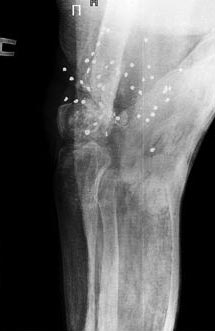

в 2009 году я получила несколько огнестрельных ранений(дробь) и одно ранение в ногу в область коленного сустава и одно ранение в ногу в область коленного сустава и вот на протяжении уже более 4 лет мне не могут помочь срастить перелом перенесла 4 операции по налажению аппарата Илизарова две операции в августе 2009 года и находилась в нем по апрель 2010 года, нога не срослась...местные республиканские врачи( проживаю в Республики Хакасии) сказали,что ни чем не могут помочь, только в 2011 году меня согласились прооперировать в клинике Илизарова в г.Кургане в 2012 году с марта месяца и по 2013 год август я находилась в аппарате илизарова за этот период, было сделано три операции, но результатов положительных это не дало в августе меня выписали с клиники сняли аппарат наложили лангету и выписали с диагнозом имеются ренгенологические признаки консолидации отломков дистального отдела правой бедренной кости,щель коленного сустава дисконгруэнтна так же имеются множественное количество инородных тел дробь..после посещения уже наших врачей они сказали что перелом не срастется совсем и сейчас я нахожусь в лангете, нога все чувствует нет свищей и нет нагноений мышцы не ослаблены я постоянно занимаюсь изометрическими упражнениями...На данный момент были сделаны снимки новые и диагноз несрастающийся перелом ,Помогите нет сил терпеть боль столько лет..прилагаю снимки ..

Ситуация здесь непростая. Стандартное эндопротезирование тут не годится, нужен ревизионный или онкологический протез, да и риск инфекции очень высок. Эндопротезирование коленного сустава делают и в Курганском РНЦ, где Вы уже были. Обсуждали там этот вариант?

Можно обсуждать артродез (замыкание) коленного сустава с остесинтезом длинным внутрикостным стержнем бедро-голень. Сравнительных снмков нет, еще и про укорочение то есть нет информации.